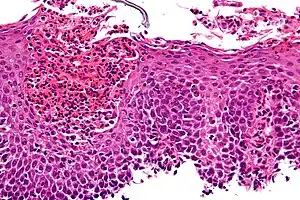

Esophagitis can be diagnosed by upper endoscopy, biopsy, upper GI series (or barium swallow), and laboratory tests.[4]

An upper endoscopy is a procedure to look at the esophagus by using an endoscope. While looking at the esophagus, the doctor is able to take a small biopsy. The biopsy can be used to confirm inflammation of the esophagus.